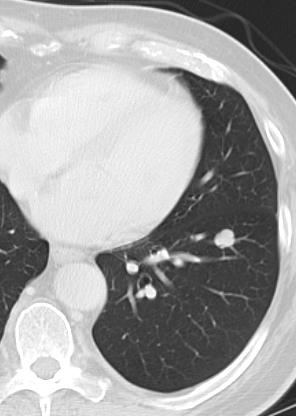

肺肿瘤消融技术

3. 针道/和最小通过距离(needle trajectory/ minimize needle passes)